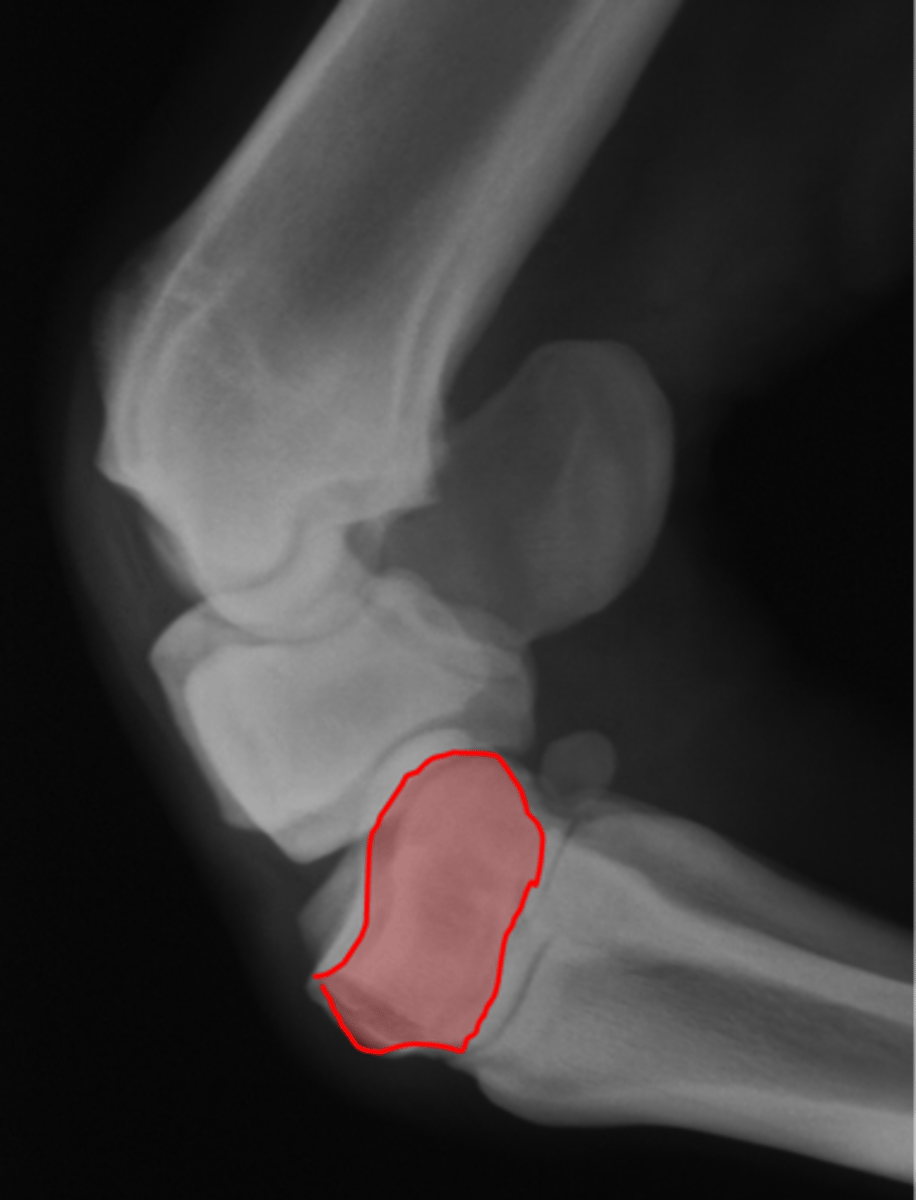

Navicular bone

Proximal border

Flexor surface

Distal border

Articular border

Navicular bone

Flexor cortex

Navicular bone

Proximal border of navicular bone

Distal border of navicular bone

Synovial invaginations

Flexor skyline

What view is this?

1. Flexor surface

2. Corticomedullary distinction

3. Number of synovial invaginations

What is the flexor skyline used to evaluate?

Navicular bone

Articular surface of navicular bone

Flexor surface of navicular bone

Sagittal ridge

Synovial invaginations

Palmar process of P3

Palmar aspect of P2